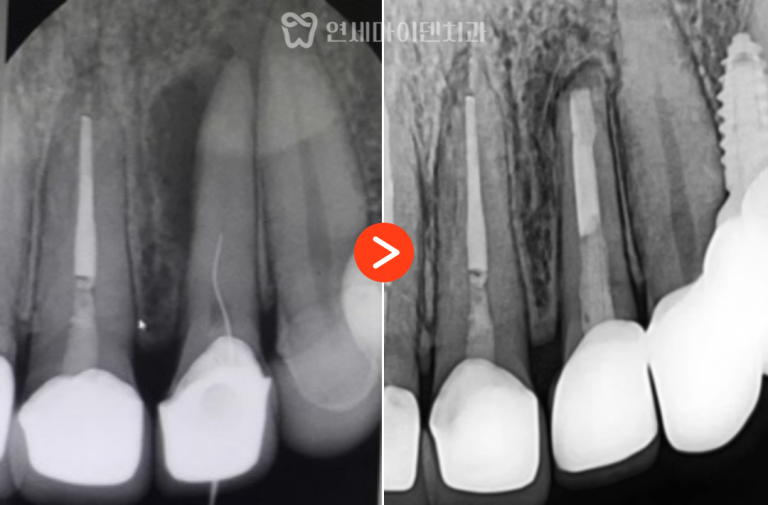

과거 신경치료를 확인해보니,

신경관 충전이 뿌리 끝까지 도달하지 못한 상태였습니다.

충분히 개선 가능성이 있다고 판단하여 재신경치료를 진행했습니다.

26번 치아 — 발치 즉시 임플란트

그러나 바로 뒤쪽의 #26번 치아는 상황이 달랐습니다.

보철물을 제거하자 내부에서 출혈이 계속되어 CT를 재확인했더니

구개측 뿌리(perforation)가 뚫린 상태였습니다.

염증으로 인해 주변 뼈 손실이 심했고,

이미 MTA(특수 치근 수복재)를 적용하기엔

시기를 놓친 상태였습니다.

수술은 뼈 보존을 고려해 즉시 식립 후

안정적으로 골유착을 유도하였고,

3년간의 추적 관찰 결과, #26번 임플란트는

주변 잇몸과 뼈의 안정성이 매우 양호한 상태로 유지되고 있습니다.

#25번 재신경치료 부위 역시 염증이 완전히 소실되어,

통증 없이 자연치아처럼 사용 중이십니다.